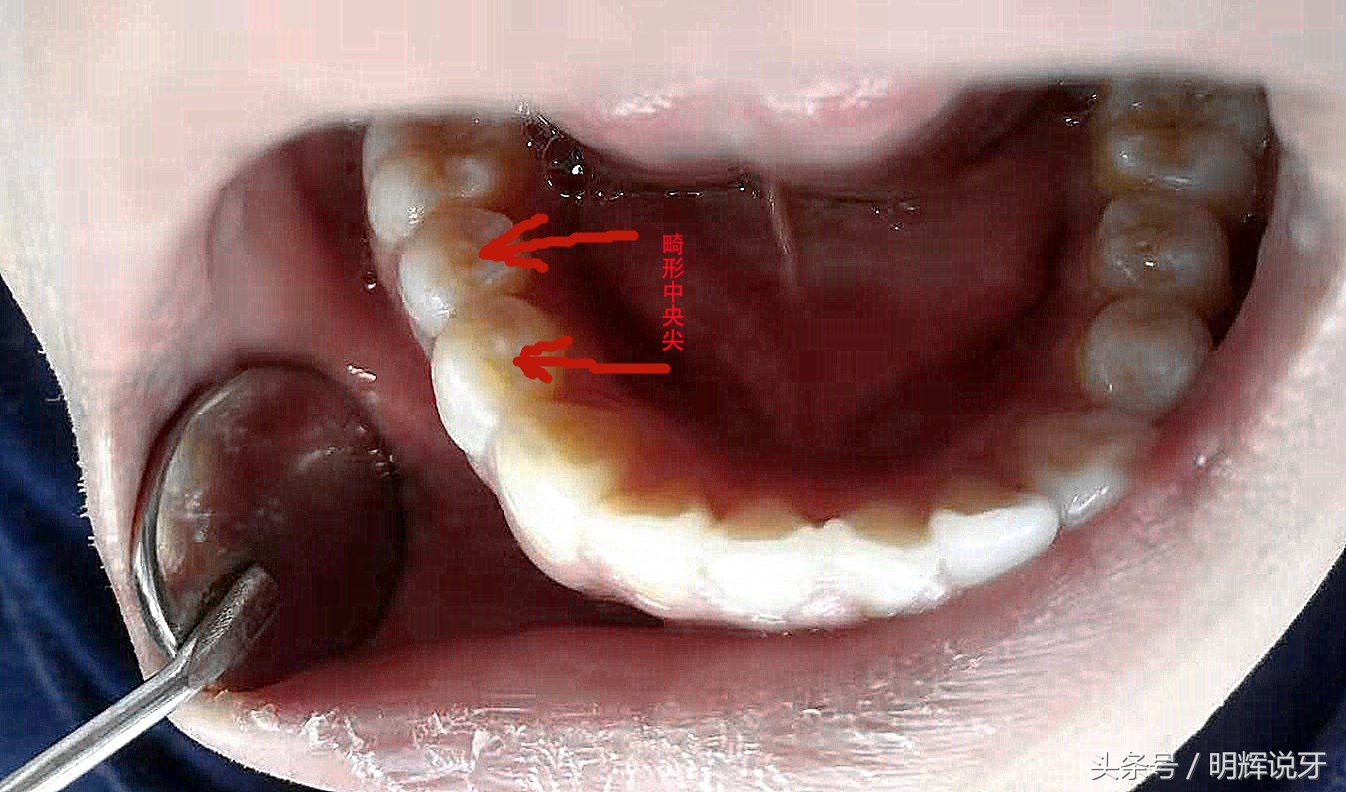

但是有些牙尖,让人烦恼,虽然你也不想见他,但是他确随你而来,你只能接受,因为他是天生的畸形,又称畸形中央尖,常见于前磨牙,突出在牙齿的最中间!

畸形中央尖